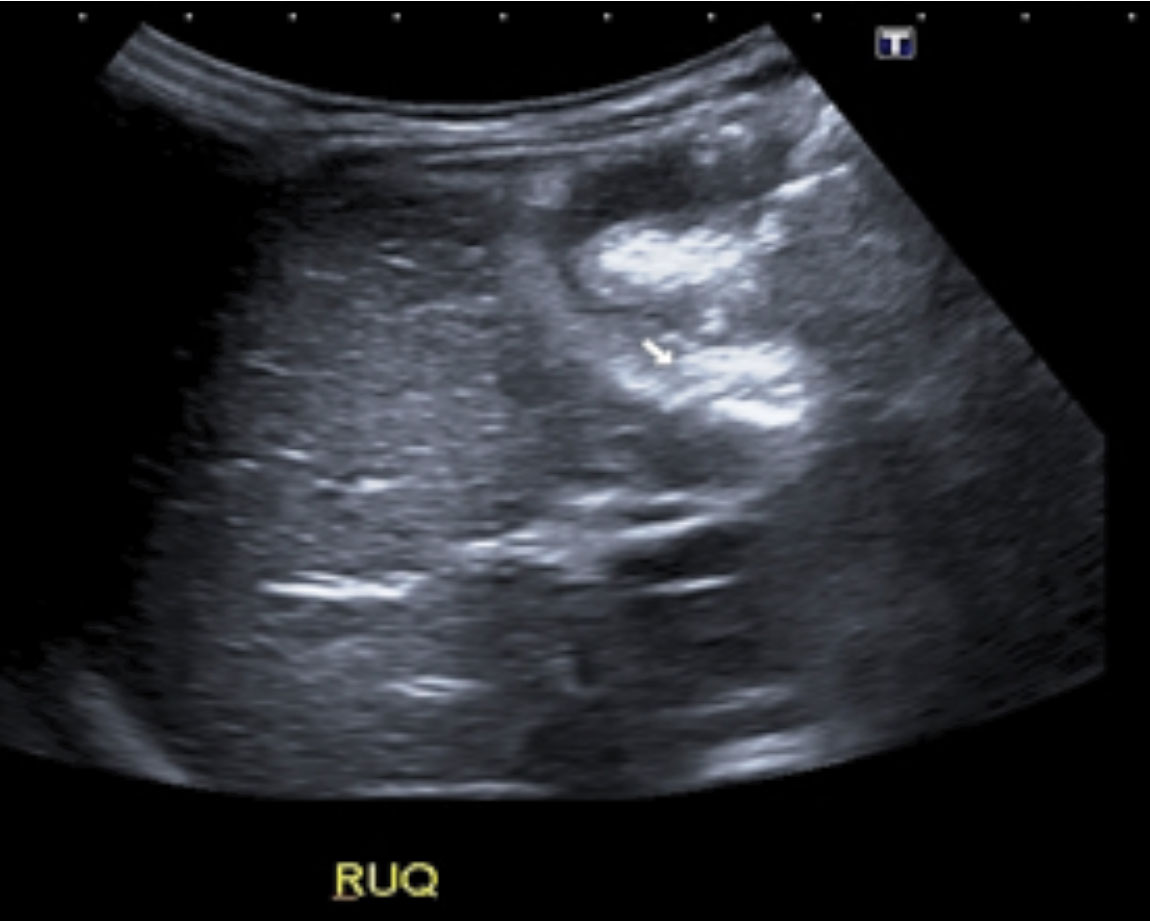

US abdomen showed free fluid in the hepatorenal recess. A thick-walled oedematous tubular structure consistent with an inflamed appendix was observed in right flank anterior to the mid pole of the right kidney. This tubular structure appeared to be continuous with a tubular structure immediately inferior to it that contained at least four calcified densities. Therefore, diagnosis of perforated appendicitis with multiple faecolith was made.